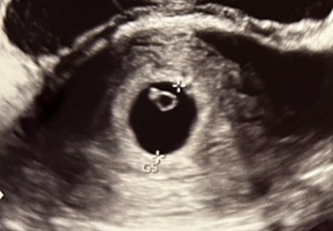

検診で確認できたこと

この日の診察で確認できたのは、

- 胎嚢:15.4mm

- 心拍:画面の中で、ぴょこぴょこ動く赤ちゃんの姿

前回胎嚢8.0mmで不安でしたが、この時期の胎嚢は1日1mm程度のスピードで大きくなっていくようです。

7日経って、胎嚢サイズが15.4mm。

ちょうど1日1mmほど大きくなっているので順調に育っているみたい。

またリングとダイヤを確認することができました。

リングの部分が赤ちゃんの栄養となる卵黄嚢

ダイヤの部分が赤ちゃん本体の胎芽です。

さらに検診の際にぴょこぴょこと小さく動く赤ちゃんの心拍を見せてもらえたそうです。